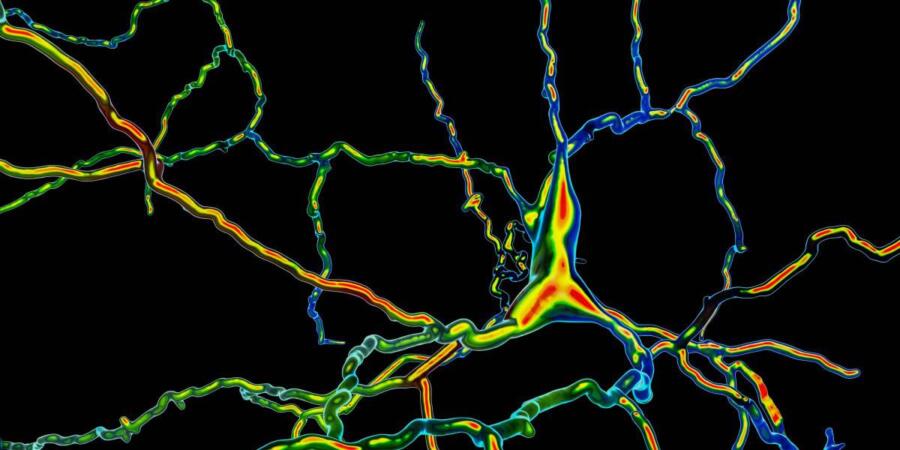

يُفترض أن تفرز الخلايا المضافة الناقل العصبي الذي يحمل اسم "الدوبامين" والذي يؤدي النقص في نسبته إلى ظهور الأعراض الوخيمة لداء باركنسون؛ مثل المشكلات الحركية.

زيادة في عدد الخلايا المفرزة للدوبامين

يتحقق الباحثون من بقاء الخلايا المزروعة على قيد الحياة من خلال حقن مادة مشعة سلف للدوبامين ثم مراقبة معدل امتصاصها في أدمغتهم باستخدام ماسح التصوير المقطعي بالإصدار البوزيتروني؛ وذلك لأنهم لا يستطيعون رؤية هذه الخلايا مباشرة بمجرد زرعها في أدمغة المرضى. بالنسبة إلى باركر؛ لم تكن هذه النتائج رصينة للغاية، وهو يقول إنه "ما يزال من السابق لأوانه معرفة" ما إذا كانت الخلايا المزروعة نجحت في ترميم التلف في أدمغة المرضى.

اكتشاف الخلايا الجذعية الجنينية هو ما جعل إجراء الاختبارات الأدق ممكناً، ويمكن إكثار هذه الخلايا وتحويلها إلى مليارات الخلايا التي تركّب الدوبامين.